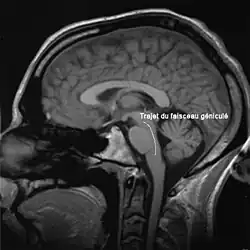

Le faisceau cortico-bulbaire relie le cortex moteur aux noyaux, origines des nerfs crâniens, dans le tronc cérébral. Dans son chemin, il traverse le genou de la capsule interne, ce qui lui vaut le qualificatif de « géniculé ».